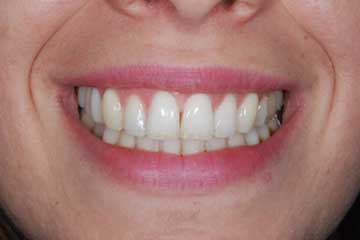

Faccette estetiche in ceramica